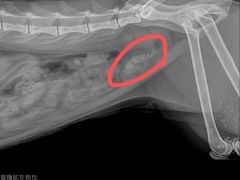

大圆_2963 | 25-08-11

报错

• -拜鲁耶动物诊疗中心·宠家动物医院